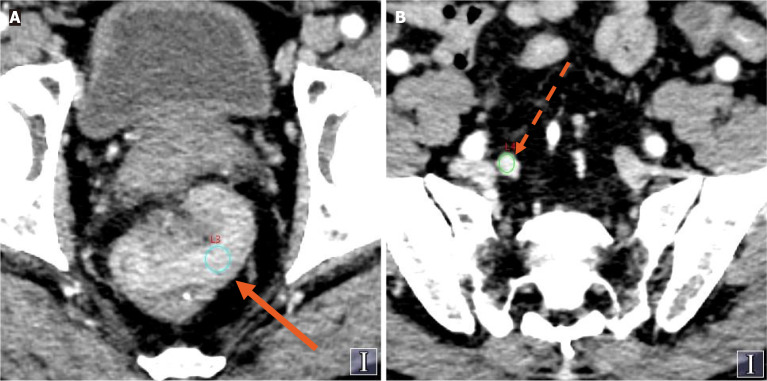

Methods: A retrospective analysis was conducted which included 121 patients with CRC whose complete spectral CT data were available. Patients were divided into the TDs+ group and the TDs- group on the basis of their pathological results. Spectral CT parameters of the primary CRC lesion and the largest regional LNs were measured, including the normalized iodine concentration (NIC) in both the arterial and venous phases, and the LN-to-primary tumor ratio was calculated. Statistical methods were used to evaluate the diagnostic efficacy of each spectral parameter.

Results: Among the 121 CRC patients, 33 (27.2%) were confirmed to be TDs+. The risk of TDs positivity was greater in patients with positive LN metastasis, higher N stage and elevated carcinoembryonic antigen and cancer antigen 19-9 levels. The NIC (LNs in both the arterial and venous phases), NIC (primary tumors in the venous phase), and the LN-to-primary tumor ratio in both the arterial and venous phases were associated with TDs (P < 0.05). In multivariate logistic regression analysis, the arterial phase LN-to-primary tumor ratio was identified as an independent predictor of TDs, demonstrating the highest diagnostic performance (area under the curve: 0.812, sensitivity: 0.879, specificity: 0.648, cutoff value: 1.145).